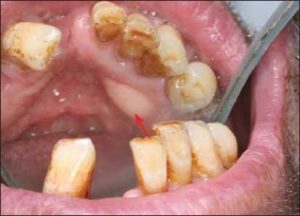

Impacted teeth located in edentulous areas and exhibiting pathological findings (Figure 10-3) should be removed, similar to retained roots. However, asymptomatic impacted teeth that are completely surrounded by bone may be retained—especially in older patients—in order to preserve arch morphology, provided that the patient is properly informed and the condition is monitored.